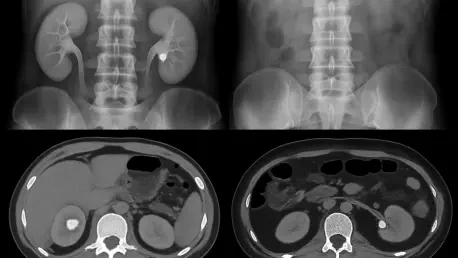

In response to these growing concerns, researchers at the Yale School of Medicine initiated a direct comparison between the established standard-dose CT scans and their low-dose counterparts to determine if patient safety could be improved without compromising diagnostic accuracy. A standard CT scan for suspected kidney stones typically exposes a patient to 10-12 millisieverts of radiation, a significant dose when accumulated over multiple procedures. The research revealed a pivotal finding: low-dose CT imaging demonstrated 100% sensitivity for detecting ureteral stones larger than five millimeters. This is a critical detail, as these larger stones are the ones most likely to cause severe obstruction and require surgical intervention. While the low-dose protocol did occasionally miss smaller stones, these are generally managed through observation and pain control rather than invasive procedures, making their immediate detection less critical. Furthermore, the study addressed concerns about overlooking other serious diagnoses, finding that the risk was minimal, at only 2-3%. In such rare cases, persistent or worsening symptoms would almost certainly prompt follow-up imaging, ensuring significant issues were not ultimately missed.